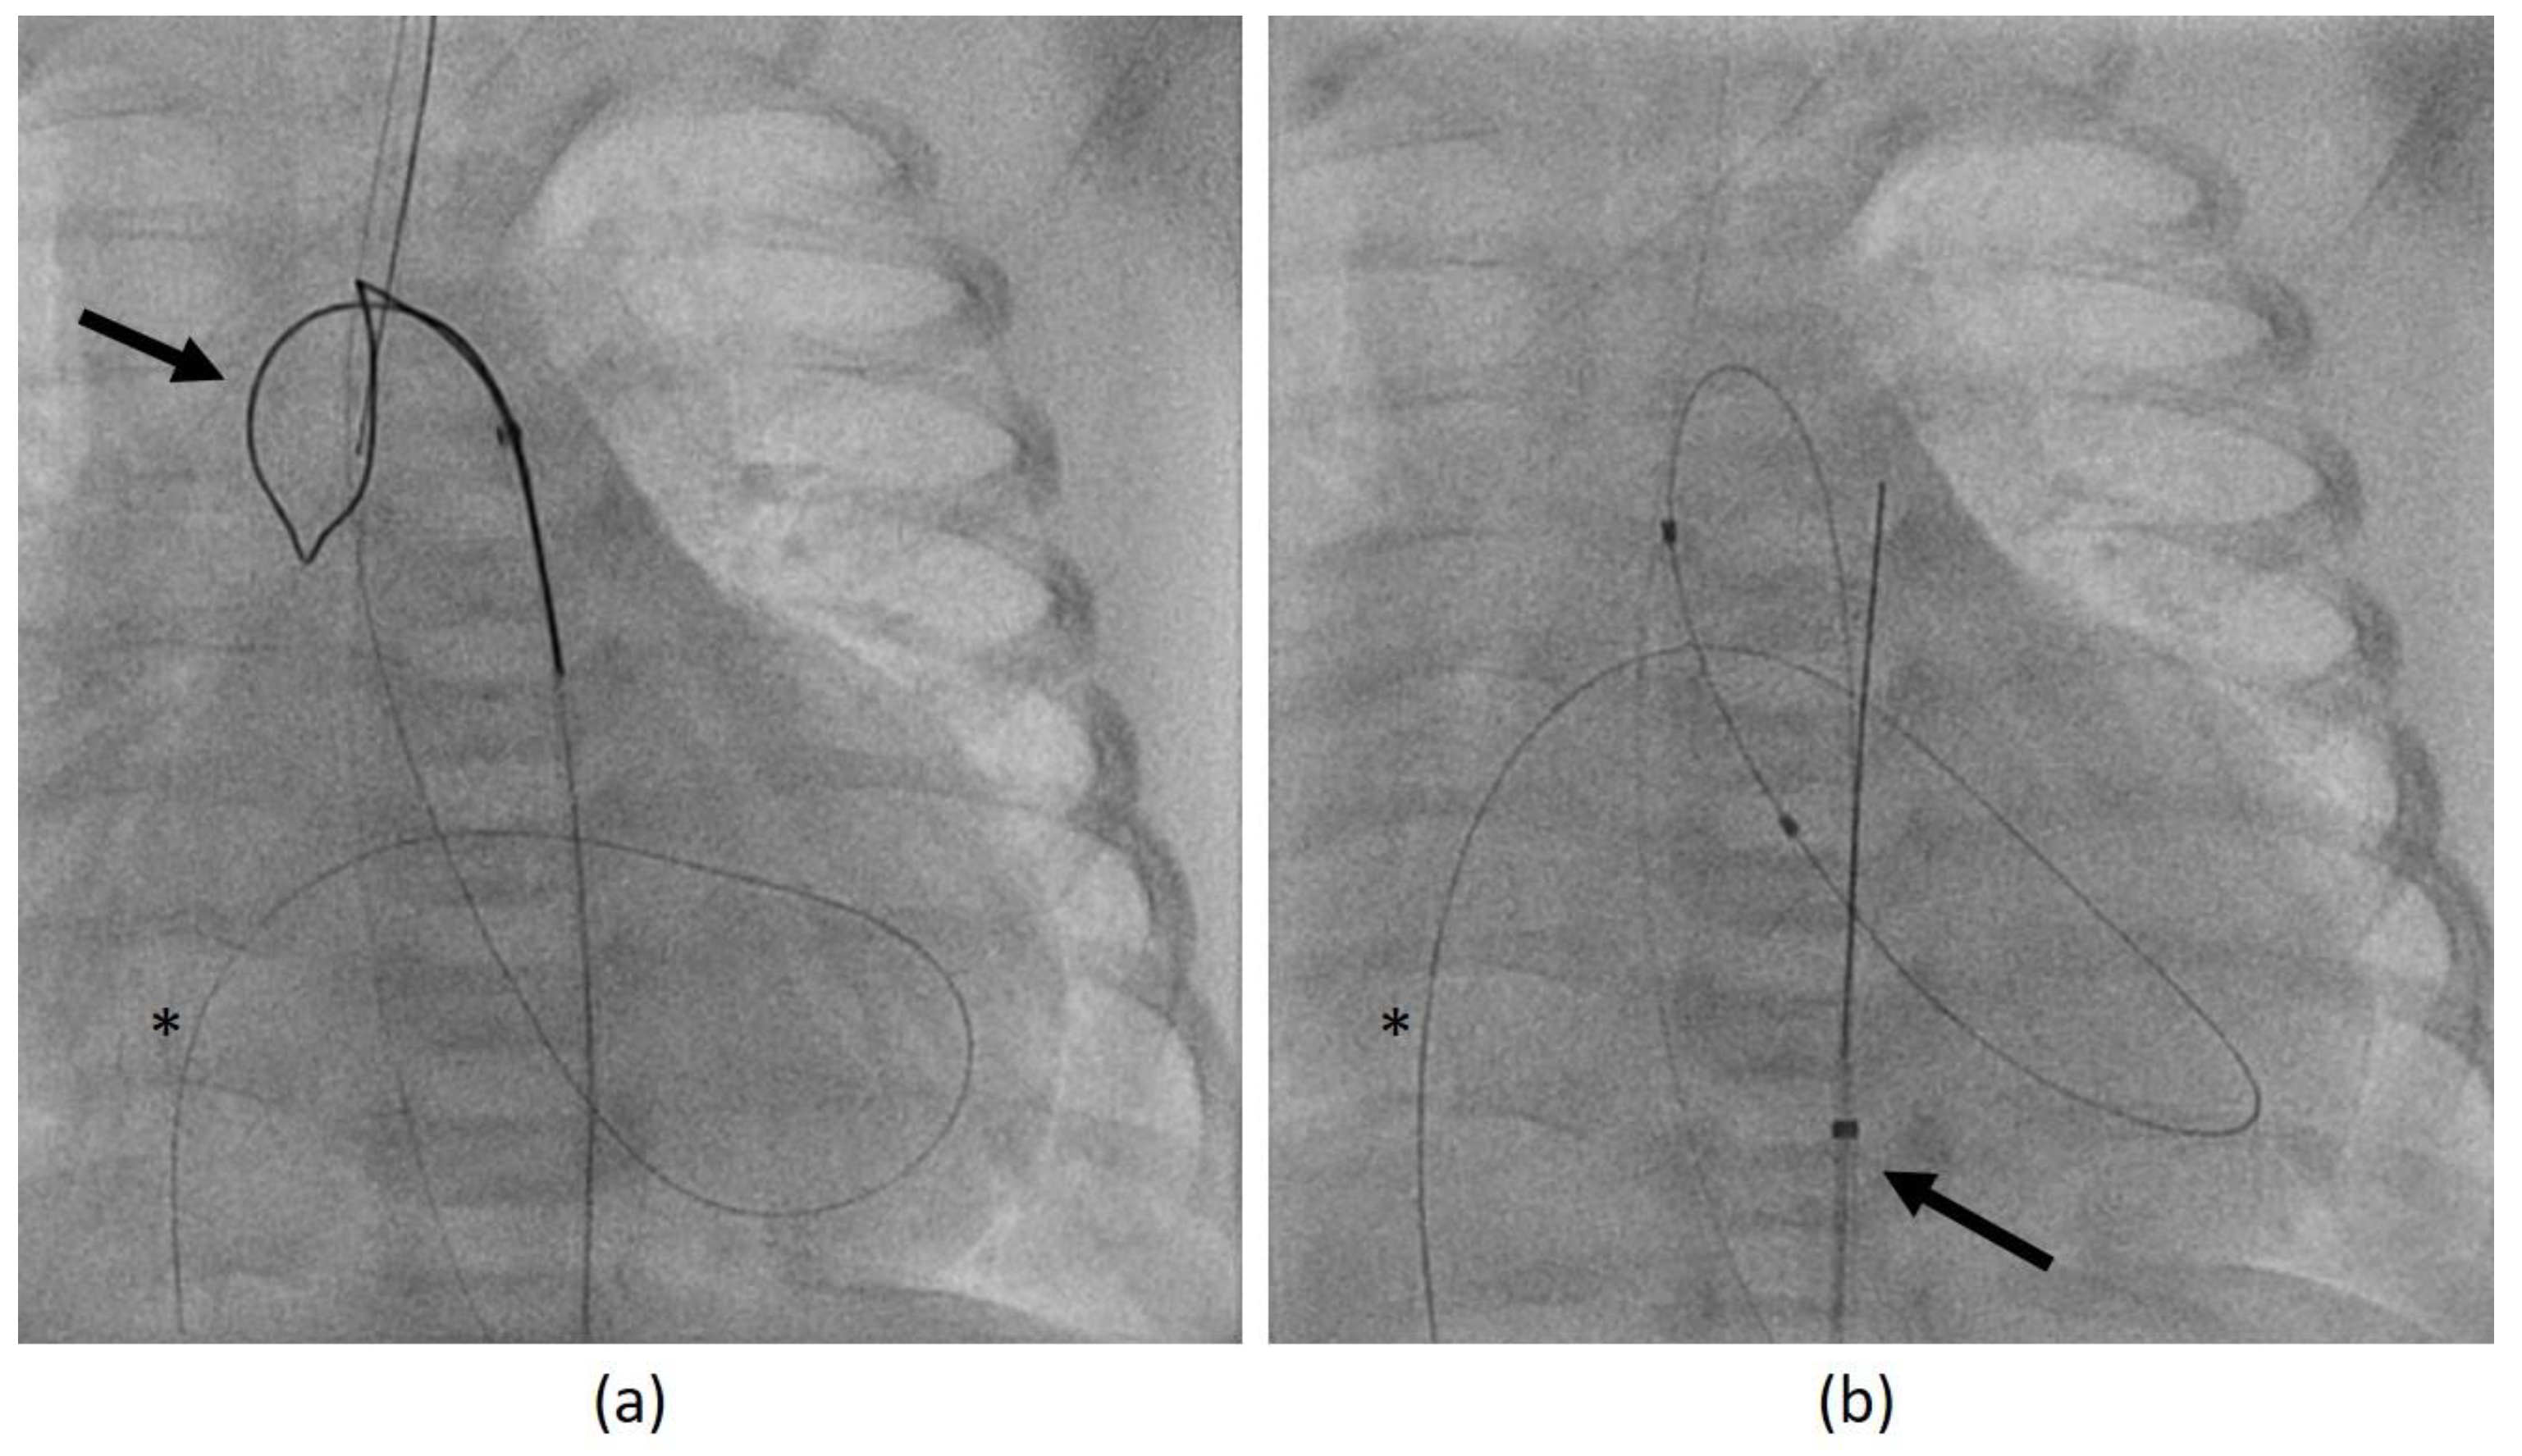

- In the same patient, an aortic wall injury resulting in a constriction of the intima following the second BAV occurred (Figure 9). However, this constriction was without significant stenosis and was corrected at the time of necessary aortic valve repair.